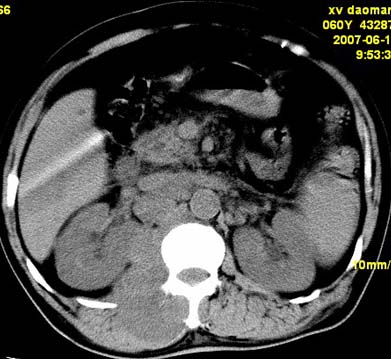

以下是引用还珠格格在2007-6-26 15:05:00的发言:[br]右侧腰大肌、同侧竖脊肌明显肿胀,呈不均匀密度减低影,右肾受压右上前移,脂肪间隙部分消失,另左侧肾盂内可见高密度影,是结石还是造影剂? 不知道病人用造影剂没有?考虑 右侧腰大肌及右侧竖脊肌寒性脓肿形成。[br][br][本贴已被 还珠格格 于 2007-6-26 15:21:35 修改过]

以下是引用刘明在2007-6-26 16:00:00的发言:[br][br]右侧竖直肌及腰大肌肿胀,脂肪间隙难辨,腹膜后血管旁见多个肿大淋巴结影,椎体附件右侧有压迫吸收、未见硬化迹象,考虑椎旁冷脓肿可能[br]左侧肾盂内可见高密度影,周围有毛刺,本图象是平扫,不是增强,应该是结石[br]

以下是引用hhcckk在2007-6-27 9:41:00的发言:[br]肾周筋膜增厚,胰腺影肥大,楼主是考我们了,我考虑是胰腺炎引起的腰部感染,形成的蓝棕色斑,也称gray-turner征,另外腹膜后怎么这么多的淋巴结,转移也要考虑[br]结核三个月没有骨破坏?寒性脓肿累及到竖脊肌的少见,所以我考虑结核的可能性不太大[br]左肾内高密度影,密度不太均匀,左肾有积水的表现,考虑是结石[br]期待楼主老师的结果